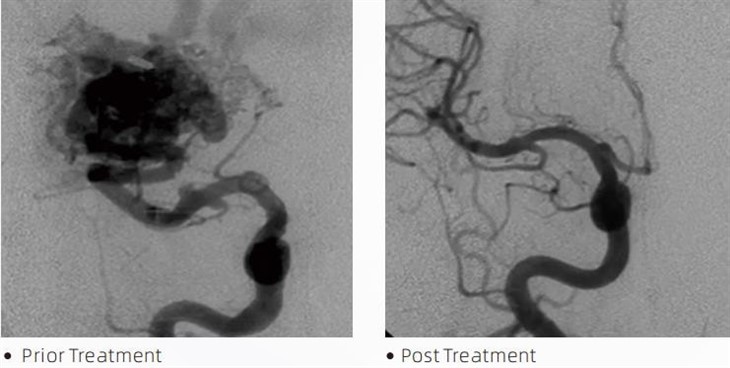

LaavaTMembolinen liima on lääketieteellinen laite, jota interventiohermoradiologit käyttävät minimaalisesti invasiivisten toimenpiteiden aikana sairauksien, kuten aivojen aneurysmien, arteriovenoosien epämuodostumien ja kasvainten hoitoon. Lava-emboliliima tarjoaa useita etuja sekä lääketieteen ammattilaisille että potilaille turvallisuuden, helppokäyttöisyyden ja tehokkuuden osalta. Laava pystyy sulkemaan verisuonet nopeasti ja tehokkaasti. Prosessi sisältää liiman injektoinnin suoraan kohdesuoneen, jossa se polymeroituu ja kovettuu valumaiseksi massaksi, joka täyttää aneurysman tai epämuodostuman. Sitten se katkaisee tehokkaasti verenvirtauksen vaurioon estäen sitä repeytymästä ja vähentäen pysyvien vaurioiden tai aivohalvauksen riskiä. Laava sisältää Lavan-12, Lavan-18 ja Lavan-34. Jokainen formulaatio on suunniteltu vastaamaan erityisiä kliinisiä tarpeita. Lava-18 on vakioformulaatio yleiseen käyttöön. Lava-34 on korkeaviskositeettinen liima suurivirtausastioihin. Lavalla-12 on pienempi viskositeetti ja se on juoksevampaa, mikä mahdollistaa distaalisten mikrosuonten muodostumisen. Näillä vaihtoehdoilla interventiohermoradiologit voivat valita sopivat Lava-formulaatiot varmistaakseen optimaalisen lopputuloksen. Yksi Lavan merkittävimmistä ominaisuuksista on sen tarttumattomat ominaisuudet. Tämä aine on erityisesti suunniteltu pysymään stabiilina, kunnes se saavuttaa kohdealueen. Tämä ominaisuus tarkoittaa, että Lava-emboliliima voidaan sijoittaa tarkasti valtimoon ja pysyä siellä tarttumatta tai kiinnittymättä ympäröivään kudokseen.